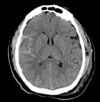

Subdural on CT head

Extradural on CT head

Subarachnoid haemorrhage on CT head

SAH

Left subdural with some midline shift

Subdural haematoma